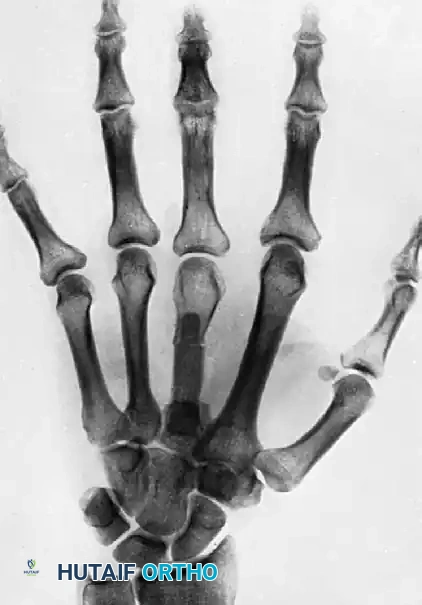

التصوير بالأشعة السينية

تعتبر الأشعة السينية (X-rays) الأداة الأساسية لتشخيص سوء التحام العظام. يطلب الطبيب صوراً من زوايا متعددة (أمامية، جانبية، ومائلة) لتقييم زاوية التشوه بدقة، وتحديد موقع الكسر القديم، وتقييم جودة العظم المحيط.